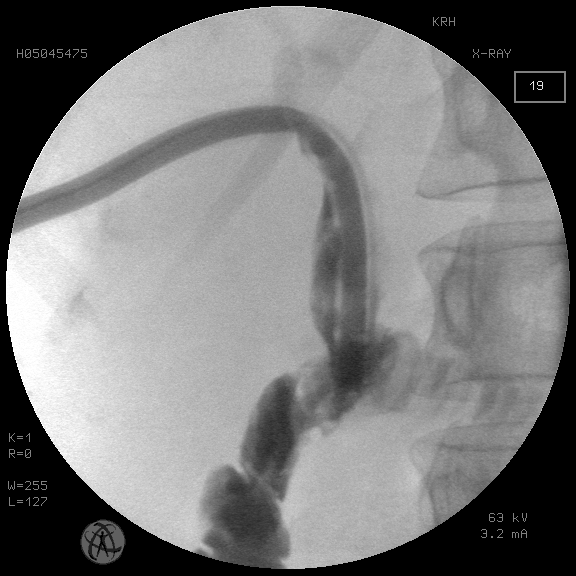

Рис. 1. Множественный мегахолангиолитиаз проксимальнее стриктуры БДА. Состояние после чрескожной чреспеченочной холангиостомии

Fig. 1. Multiple megacholangiolithiasis proximal to the stricture of the BDA. Condition after percutaneous transhepatic cholangiostomy

Группу исследования составили 16 пациентов со стриктурами БДА, осложненными холелитиазом. В трех случаях удалось низвести конкременты общего печеночного протока в отводящую кишку после баллонной дилятации стриктуры БДА. В 13 наблюдениях при мегахолелитиазе потребовалась этапная модификация пункционного холангиостомического доступа в чрескожный рентгенохирургический доступ диаметром 9 мм для последующей контактной механической и пневматической литотрипсии и литоэкстракции (рис. 1–5).

Случаи сочетания рубцовой стриктуры БДА с холелитиазом рассматриваются отдельно. Традиционно холелитиаз, осложняющий стриктуру БДА, рассматривается как фактор, предполагающий хирургическую реконструкцию анастомоза. Тем не менее необходимо отметить, что факт наличия конкрементов проксимальнее зоны БДА еще не является основанием для безусловного отказа от использования рентгенохирургических методик разрешения холелитиаза. Как показали результаты использования антеградного чреспеченочного доступа в желчное дерево с последующей контактной литотрипсией у пациентов группы исследования, полное освобождение желчного дерева от конкрементов было достигнуто у всех больных. При этом использовалась экстремальная модификация первичного холангиостомического доступа до 30 Fr для последующих внутрипротоковых манипуляций с ригидным перкутанным нефроскопом под операционный кожух 24, 26 СН с контактной пневматической литотрипсией (см. рис. 1–5). Такая методика используется нами более 20 лет и зарекомендовала себя не только эффективной, но и безопасной при условии бесконфликтности первичной чреспеченочной пункции желчного дерева [Охотников и др., 2011; Охотников и др., 2012].